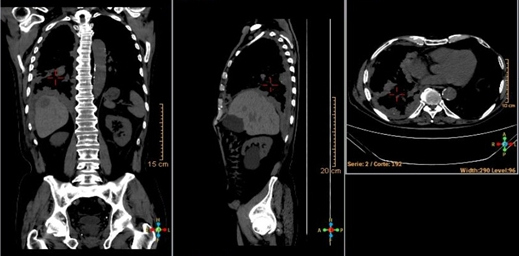

La radiografía de tórax mostró una radio-opacidad heterogénea difusa en hemitórax derecho a predominio basal, más tractos fibroticos hacia la periferia, con obturación del seno costofrénico derecho. En la TC multicorte (fig. 1) se describe una imagen densa de contornos irregulares en el segmento IV del pulmón derecho, engrosamiento pleural a predominio basal derecho, cambios intersticiales basales, adenopatías mediastinales, engrosamiento del intersticio intra e interlobulillar, bronquiectasias tubulares y quísticas en las bases, derrame pleural y lesiones focales >20 mm en el parénquima hepático compatibles con secundarismo.